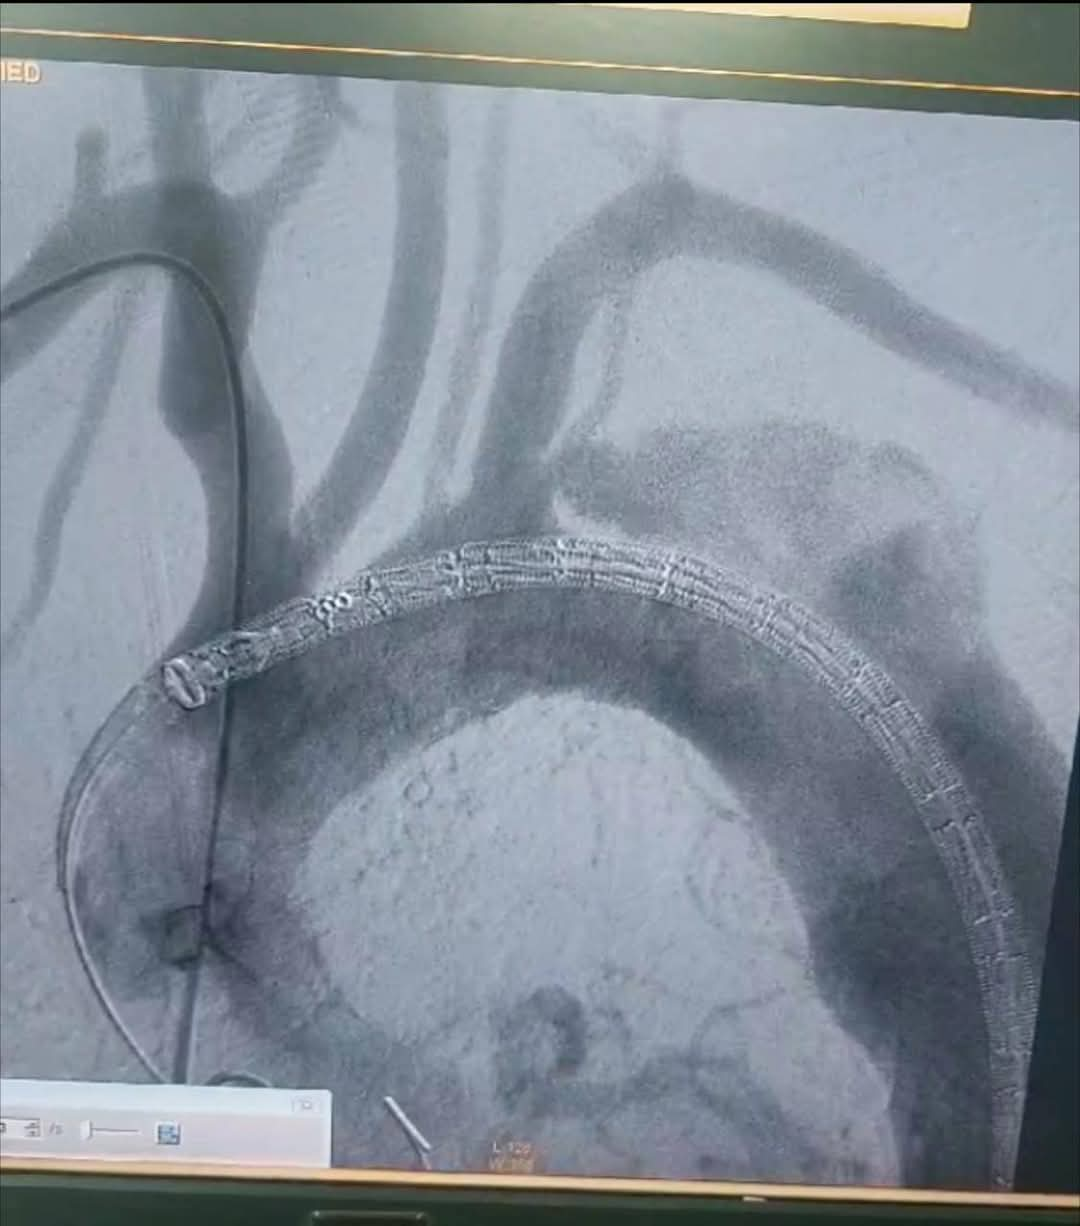

أجرى فريق أطباء قسم جراحة الأوعية الدموية بمستشفي مصر للطيران عملية إصلاح انشطار بالشريان الأورطي الصدري ممتد من الشريان تحت الترقوة الأيسر إلى شريان الحوض والفخذ الأيسر عن طريق استخدام الدعامات المغطاة Ankura™️ لتثبيت الشريان الأورطي الصدري واستعادة تدفق الدم الطبيعي.

وتم استخدام تقنية جديدة تحتاج الي مهارة ودقة عالية وللمرة الأولى في مستشفي مصر للطيران وهي عمل دعامة مغظاة فرعية لشريان الطرف العلوي الأيسر TEVAR + In situ fenestration for LSA + LSA stenting للحفاظ علي الدورة الدموية بالطرف العلوي الأيسر عن طريق عمل فتحة بالدعامة المغطاة بالشريان الأورطي الصدري باستخدام إبرة ( Futhrough™️ ) للحفاظ علي تدفق الدم بواسطة القسطرة التداخلية.